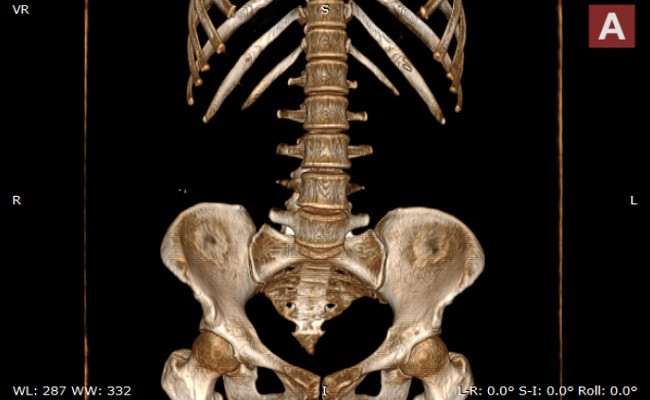

提供丰富的图像浏览功能,包括MPR、3D浏览、电影播放、伪彩、ROI测量、 HU值和SUV值测量、匿名化等

支持DICOM影像的二维显示

支持DICOM影像的MPR重建

5、点击这个按键可以3D进行浏览。